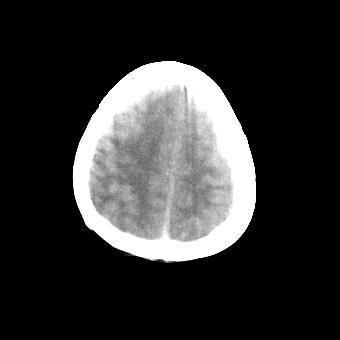

标题: CT16478:男 头晕 恶心 呕吐 [打印本页]

标题: CT16478:男 头晕 恶心 呕吐

病人不合作,图像质量差,右额叶及后纵裂可见高密度影,建议复查。

1.额叶显示密度不均匀,且右侧内见小片稍高密度影, 图像效果差些,不好定?

2.纵裂密度增高,部分脑回密度似乎也增高,蛛网膜下腔出血。

右额叶小片状高密度灶,周围有水肿带,为脑出血;是否有外伤史?若没有,则考虑肿瘤——胶质瘤出血可能性大。

病人不合作,图像模糊,大脑镰及纵裂池后部密度增高;考虑:蛛血?

右额叶片状低密度灶,其前内侧小片状略高密度,首先考虑胶质瘤

另外恶心呕吐多久,临床有无发热,年龄多大?不排除脑炎的可能

[quote]以下是引用叶子123在2008-11-13 9:55:00的发言:[br]患者因煤气中毒入院,临床及ct均诊断一氧化碳中毒性脑病[br][br]